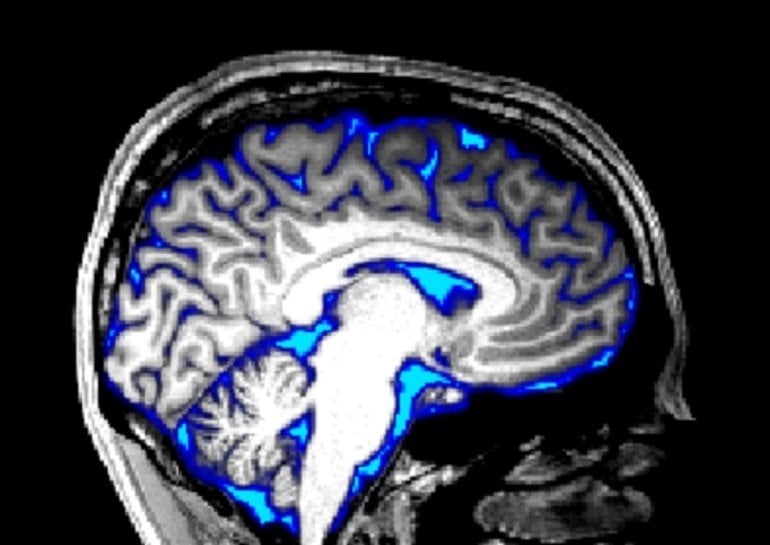

A UNSW study using MRI on 22 volunteers shows yawning shifts cerebrospinal fluid flow in the brain in a way that deep breaths do not, and also increases brain blood flow. This pattern could help cool the brain and aid waste clearance, suggesting yawning has a physiological function beyond signaling boredom or empathy. The yawning motions appear tightly coordinated by brainstem circuitry and often accompany swallowing. The work is a preprint and not yet peer‑reviewed, and further research is needed to confirm these findings in everyday life.